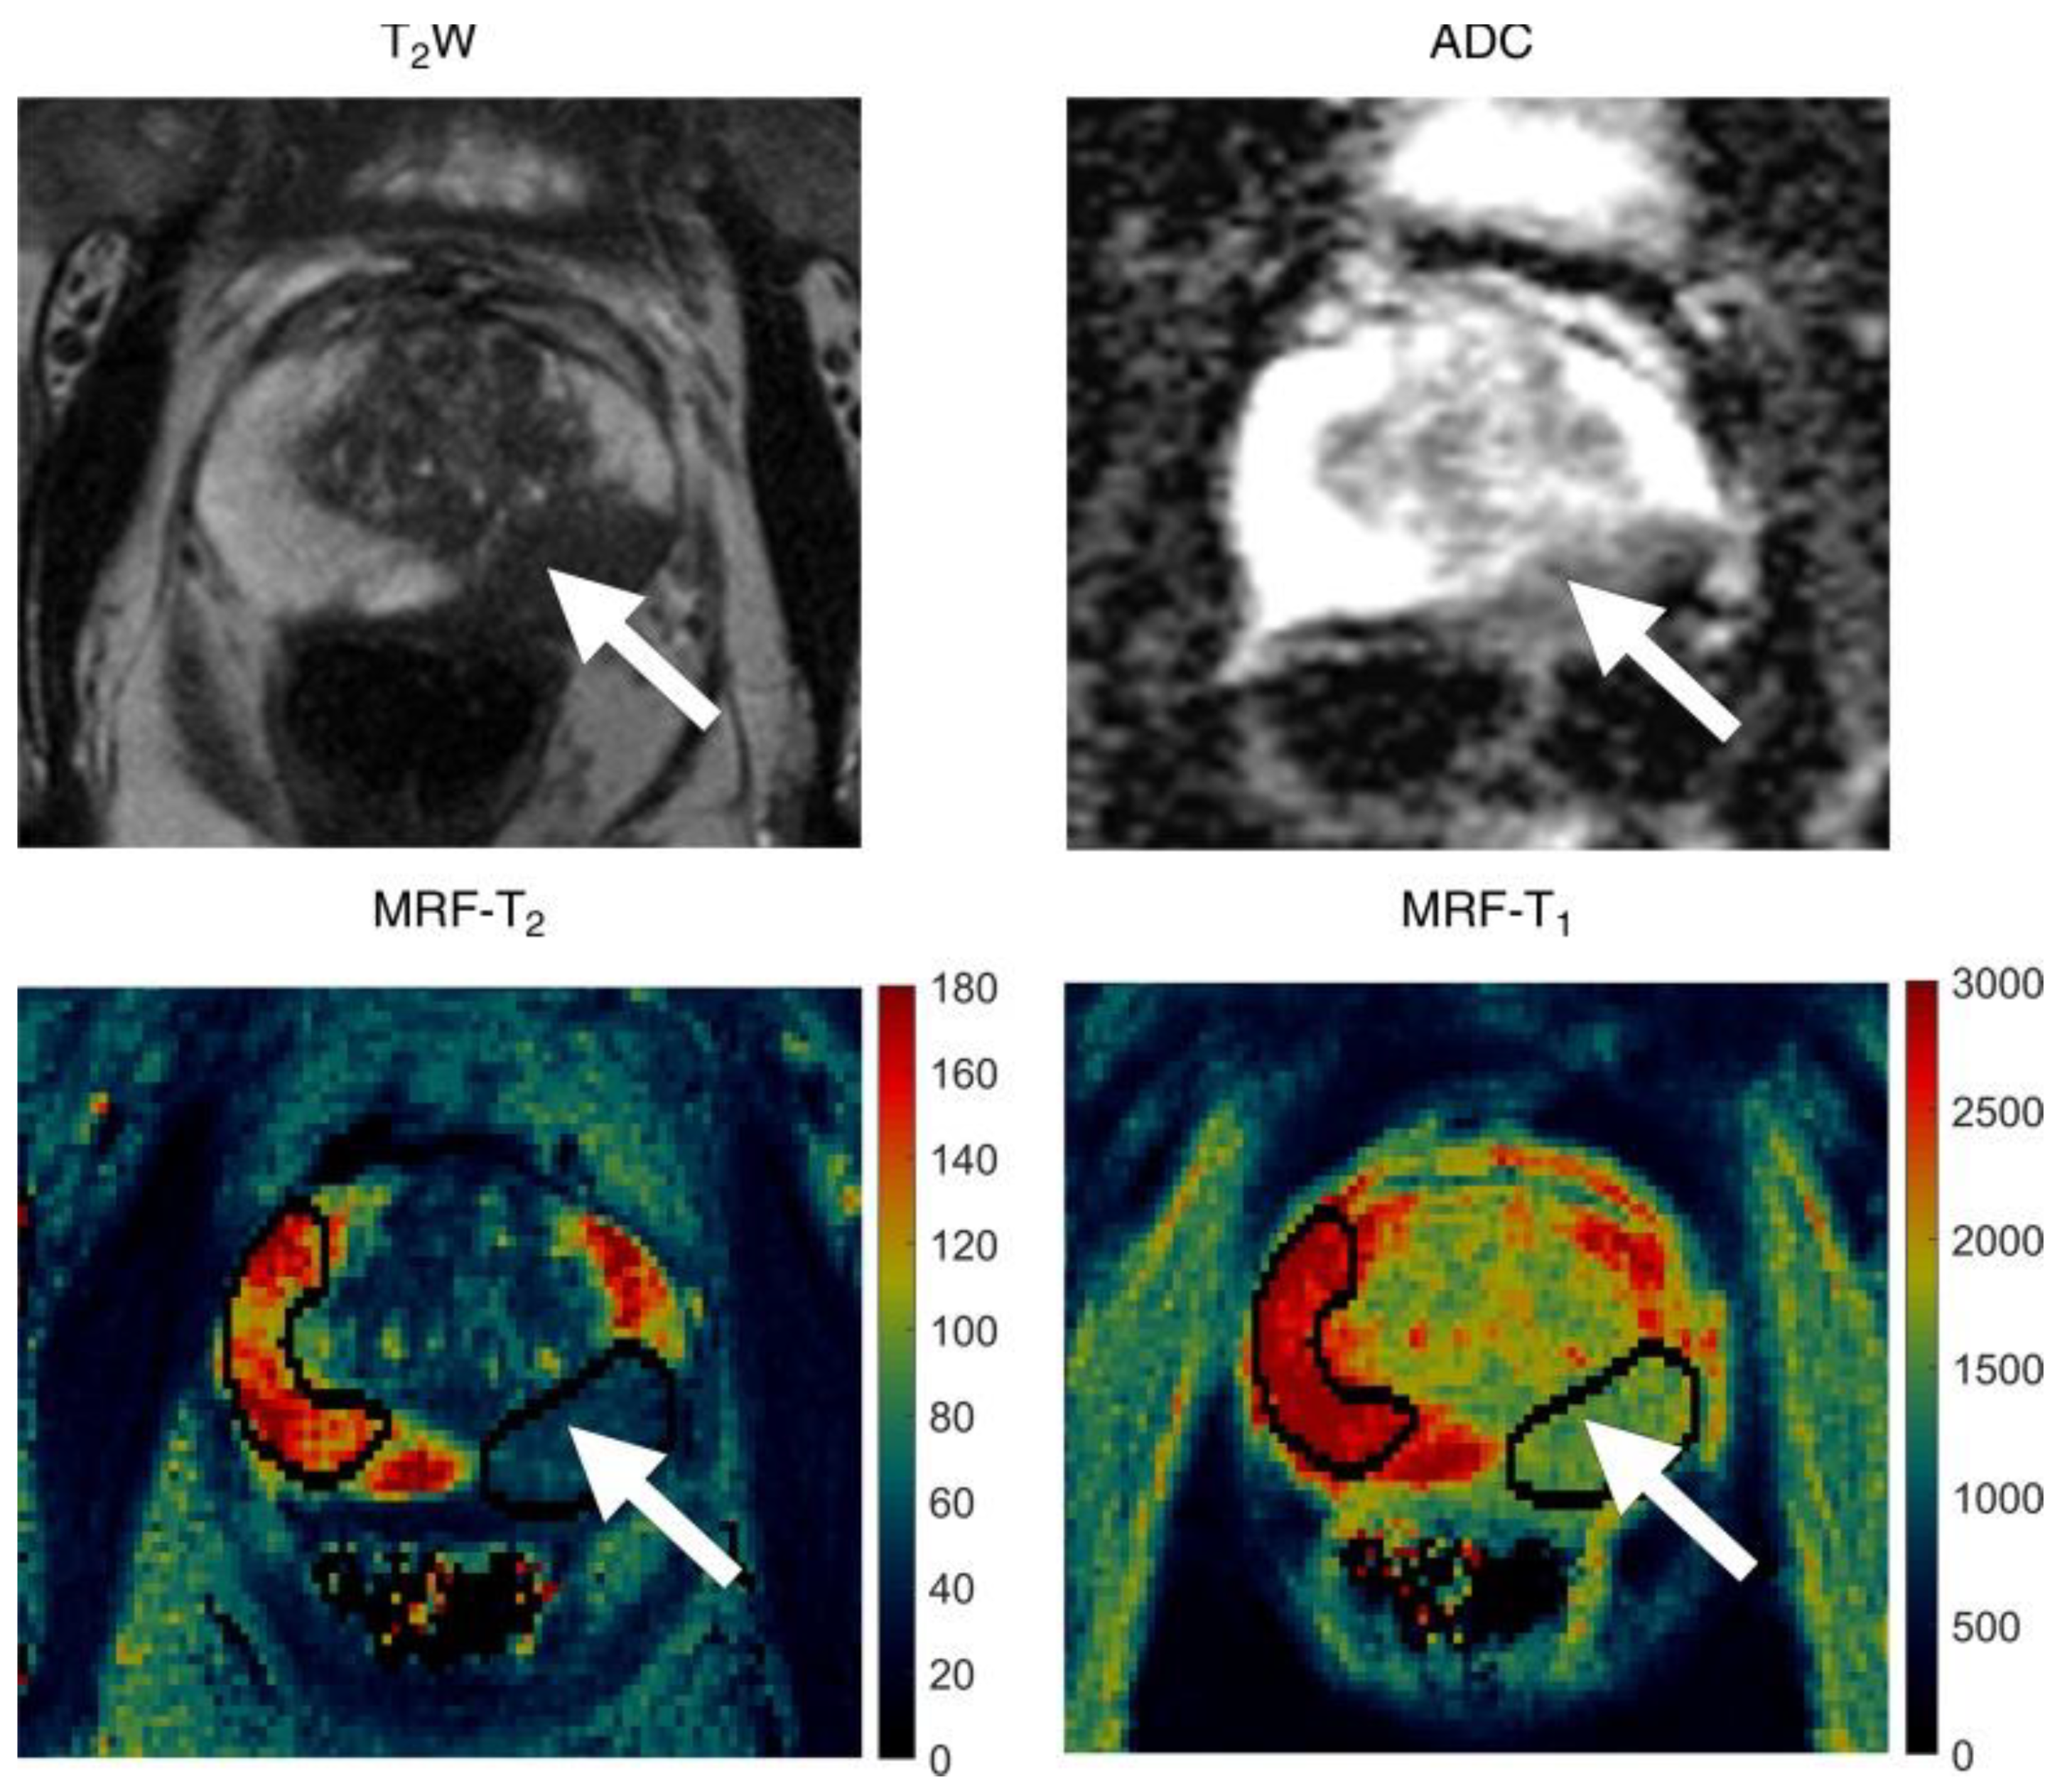

- Yu, A.C.; Badve, C.; Ponsky, L.E.; Pahwa, S.; Dastmalchian, S.; Rogers, M.; Jiang, Y.; Margevicius, S.; Schluchter, M.; Tabayoyong, W.; et al. Development of a Combined MR Fingerprinting and Diffusion Examination for Prostate Cancer. Radiology 2017, 283, 729–738. [Google Scholar] [CrossRef]

- Panda, A.; O’Connor, G.; Lo, W.C.; Jiang, Y.; Margevicius, S.; Schluchter, M.; Ponsky, L.E.; Gulani, V. Targeted Biopsy Validation of Peripheral Zone Prostate Cancer Characterization With Magnetic Resonance Fingerprinting and Diffusion Mapping. Investig. Radiol. 2019, 54, 485–493. [Google Scholar] [CrossRef]

- Panda, A.; Obmann, V.C.; Lo, W.-C.; Margevicius, S.; Jiang, Y.; Schluchter, M.; Patel, I.J.; Nakamoto, D.; Badve, C.; Griswold, M.A.; et al. MR Fingerprinting and ADC Mapping for Characterization of Lesions in the Transition Zone of the Prostate Gland. Radiology 2019, 292, 685–694. [Google Scholar] [CrossRef]